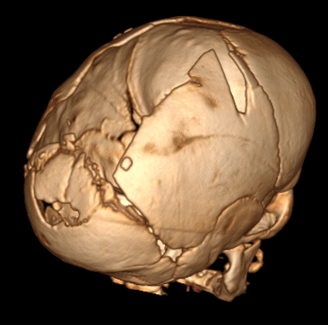

Плагиоцефалический краниосиносгоз.

Отмечается сращение левой половины венечного шва, приводящее к образованию надглазничного валика

на стороне поражения и косого положения брови на противоположной стороне.